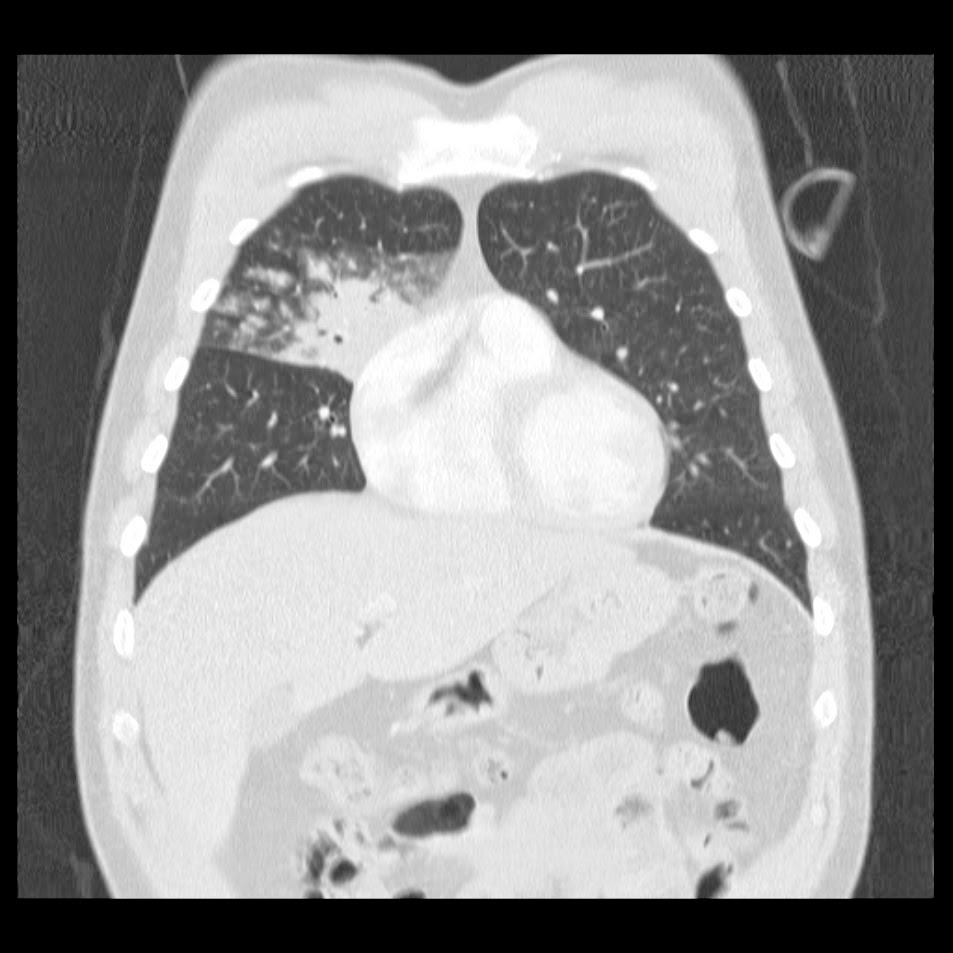

Caso interesante #6

Otro casito de un tórax para localizar la consolidación